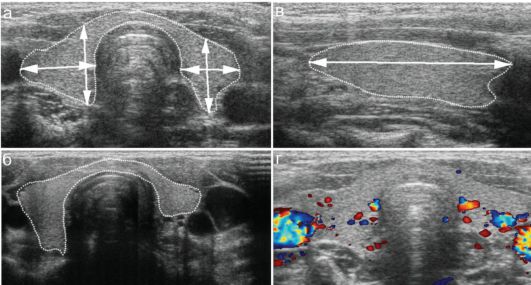

Посмотрите на фото из моего первого поста: ведь разная же методика измерения, разве не видно? И объемы получаются пусть немного, но разные! Про нормативы не будем говорить - они известны.

Аппарат может посчитать разный объем, в зависимости от последовательности измерений ( у меня так например). Наверное считает по какой-то интересной формуле. Поэтому надежней помножить на калькуляторе и на коэффициент (который в одних источниках 0.52 , а в других 0.497).

- По поводу измерения щитовидки, оба из представленных вариантов измерения допустимы, коэффициент обычно 0,479;